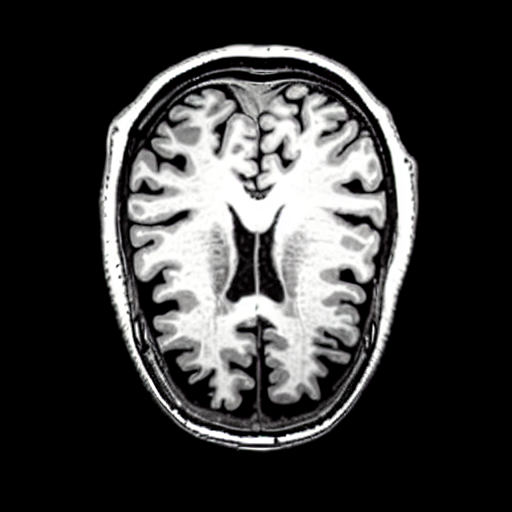

We present the results of conditional medical image generation with and without our proposed method LD, in Tab. 1, and Fig. 5. In Fig. 4, we show examples of brain MR images generated by the different methods combined with LD for two different classes of cognitively normal (CN) and Alzheimer’s disease (AD). The results were obtained by fine-tuning the corresponding method on the medical data with LD. As shown in Fig. 4, the samples generated through Custom Diffusion tuning are realistically looking while understanding the difference between CN and AD brain properly, which other methods failed at. Textual inversion seems to understand the concept but fails to understand the brain structure properly. Quantitative results on the performance of all our methods are presented in Tab. 1. Qualitative results on the CheXpert [19] dataset, along with a user study and ablation of different parameters, optimization algorithm, and more, are included in the supplementary material.

Qualitatively, Fig. 5 shows a significant improvement of the visual realism across all methods when using a drift of . The background is consistently black as in real brain MR images; the shape of the brain becomes more realistic, and the white and gray matter structure improves. For an analytical evaluation, we calculated the FID between our test data and 200 synthetically generated images from each method (100 CN, 100 AD). The results in Tab. 1 demonstrate that LD improves the ability of the model to generate realistic MRI slices for both healthy brains and brains with Alzheimer’s disease. For this reason, all following experiments were done with LD.